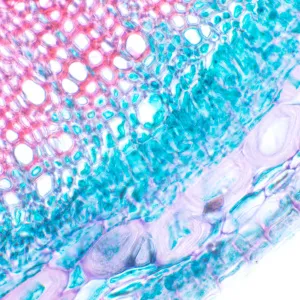

MAGUS Bio 230T – биологический тринокулярный микроскоп для лабораторных и исследовательских наблюдений в медицине, фармацевтике, криминалистике, биотехнологии и других областях науки. Применяется для работы с плоскими полупрозрачными и прозрачными образцами биологического происхождения: тонкими срезами и мазками. Оснащен ахроматической оптикой и галогенной подсветкой, наблюдения ведутся в проходящем свете в светлом поле. Микроскоп рассчитан на установку дополнительных аксессуаров для использования большего количества методов наблюдений: темного поля, фазового контраста, поляризованного света.

Цифровая камера MAGUS CDF10 с сенсором 2 Мпикс для исследования микрообъектов в темном или светлом поле. Камера оснащена цветным CMOS-датчиком SONY Exmor с технологией обратной засветки. Благодаря этому улучшается светочувствительность (2350 мВ при 1/30 с) и повышается качество изображения при слабом освещении. Оптимальная производительность достигается при работе на объективах с увеличениями 40, 60 и 100 крат.

С помощью камерыможно выводить изображение объекта на монитор компьютера в разрешении Full HD 1920x1080 пикс, снимать фото и записывать видео в разных форматах. Передача данных между камерой и компьютером осуществляется через интерфейс USB 3.0 со скоростью передачи данных 5 Гб/c. При предельном разрешении видео отображается с частотой 125 кадров в секунду, с плавными переходами между кадрами. Камера подходит для изучения движущихся объектов, ее можно использовать для проведения лекций или презентаций.